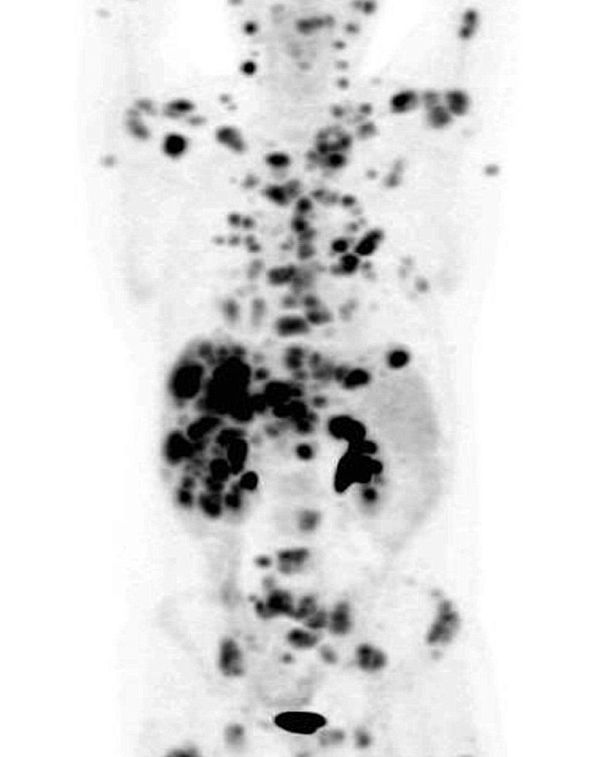

Ovviamente, la domanda posta è sbagliata in partenza, perché non esiste una sola forma di tumore, ma ne esistono moltissime e di origini diverse (virali, radiazioni, ormoni, agenti fisici e altri ancora). Nel caso in questione, si è trattato di un linfoma non Hodgkin che colpisce il tessuto linfatico e rappresenta circa il 3% dei tumori diagnosticati in Italia. Lo sfortunato Ian, che aveva già lottato con questo cancro tra il 2001 e il 2008, ha accettato la terapia a base di Brentuximab : avendo una prospettiva di vita di poche settimane, decise di non avere nulla da perdere.

Il primo dettaglio da chiarire è che non si tratta proprio di una scommessa: il medicinale è in prova da alcuni anni e i risultati per questo linfoma specifico sono stati promettenti dall’inizio, ed è dal 2012 che il farmaco sta venendo monitorato in Europa. In 12 settimane, i medici hanno riscontrato un miglioramento eccezionale, e sembrano certi della possibilità della totale guarigione di Ian.